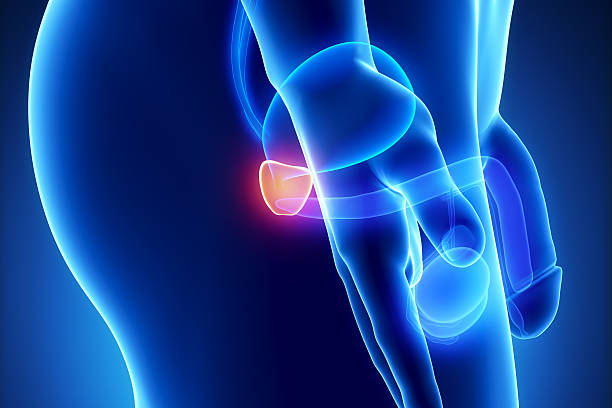

전립선비대증은 남성에서 주로 발생하는 전립선의 비대증입니다. 전립선은 남성의 생식기로서, 요도 주변에 위치하며, 요도를 통해 배뇨와 정액의 배출을 조절합니다. 전립선비대증은 나이가 들수록 발생 확률이 높아지며, 대부분의 남성이 한 번 이상 경험하게 되는 질환입니다.

전립선비대증은 전립선의 세포가 비정상적으로 증식하면서 발생합니다. 이러한 세포 증식으로 인해 전립선이 커지면서 요도 주변을 압박하고, 배뇨와 관련된 증상을 유발합니다. 전립선비대증은 일반적으로 배뇨 불편, 방광염, 자주 병원가는 등의 증상을 유발합니다.